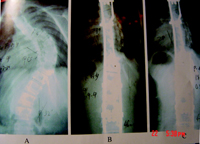

叶启彬教授等研制的PRSS装置的独有优点是:手术时不需植骨,一次手术即能满意矫正脊柱侧弯及维持矫正,也不需多次手术延伸内固定。术后PRSS能随儿童脊柱生长而自动延伸,既能矫正脊柱侧弯,又不限制脊柱长高,因此能有效防止躯干短小畸形和一部分“曲轴”现象。当骨发育成熟后,取出内固定,脊柱形态和活动接近正常。从1998年10月至今,叶启彬教授已用PRSS矫正了200余例各种类型儿童脊柱侧弯,并对其中66例随诊2年以上的特发性脊柱侧弯进行了分析,其中男性29例,女性37例,手术时平均年龄12.15岁(3~15岁),女性组均小于13岁,男性组均小于15岁。脊柱侧弯由术前66.58°40°~110°矫正至22.70°,平均矫正率68.86%。PRSS矫正节段脊柱平均增高11.13 mm,6例骨成熟取出内固定后,侧弯矫正维持良好,脊柱活动度接近正常。